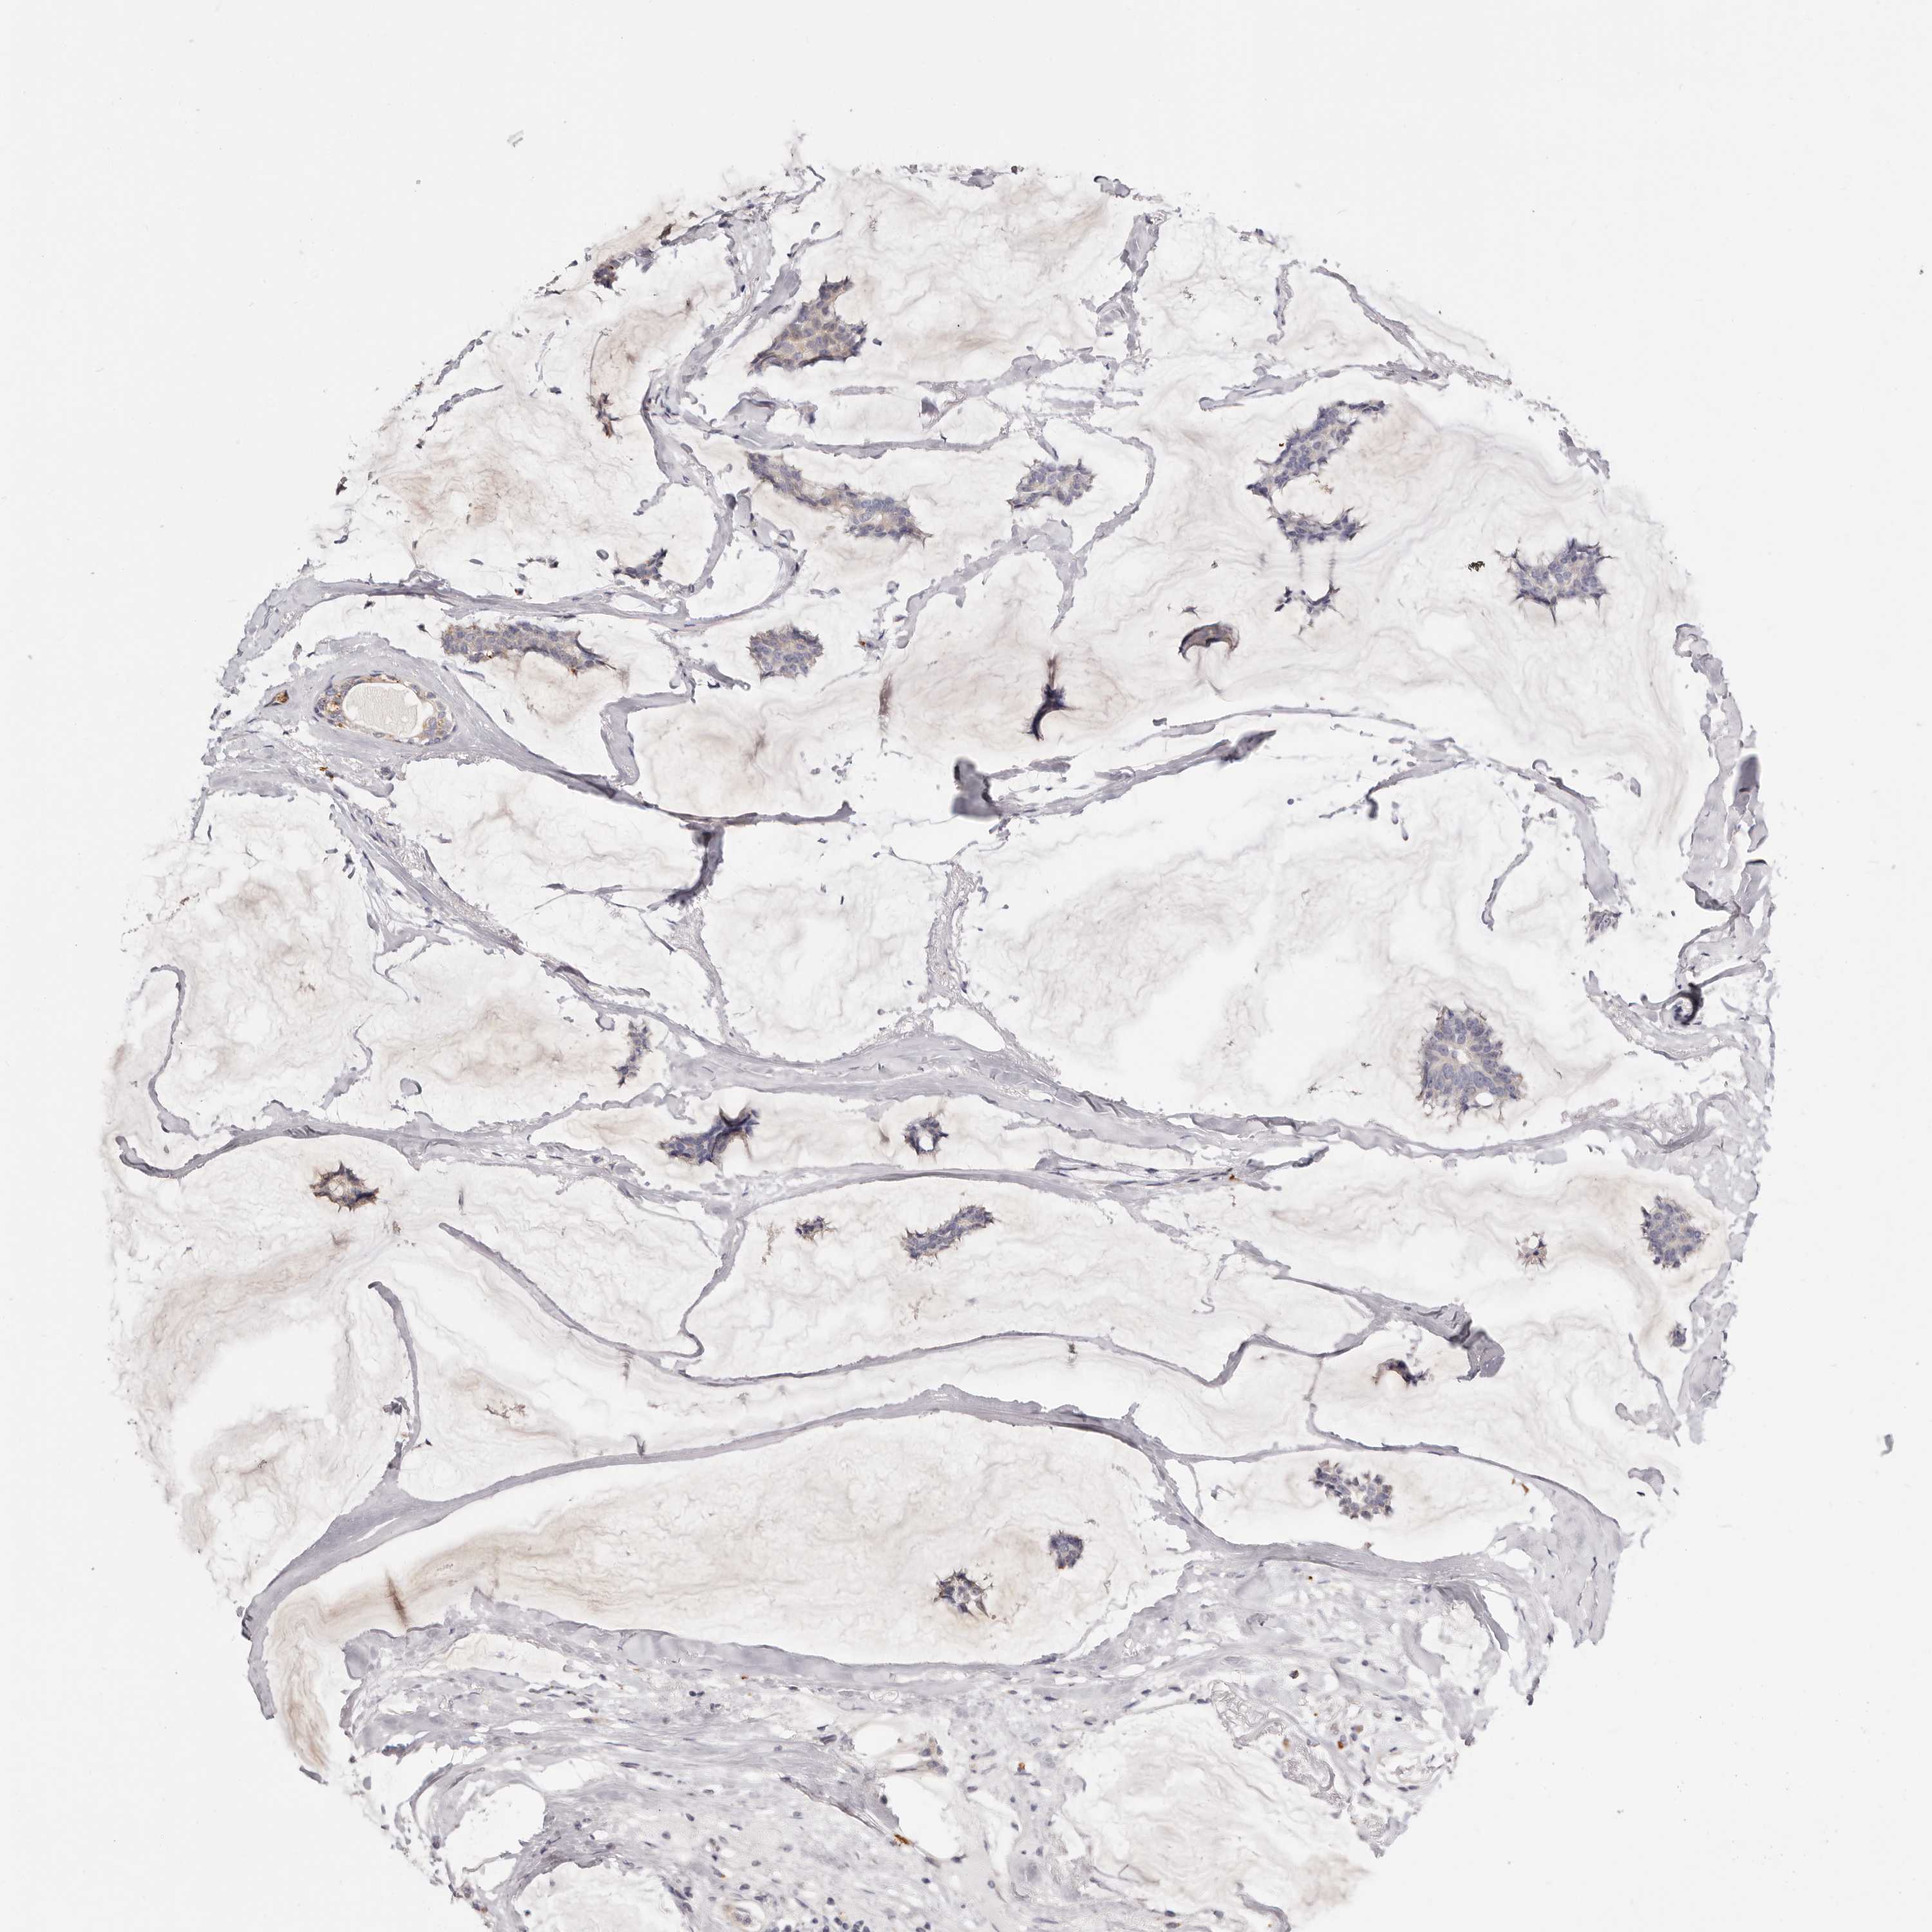

CANCER BREAST CANCER Show tissue menu

BRCA TCGA BRCA VALIDATION PROTEIN EXPRESSION

ANTIBODIES

AND

VALIDATION